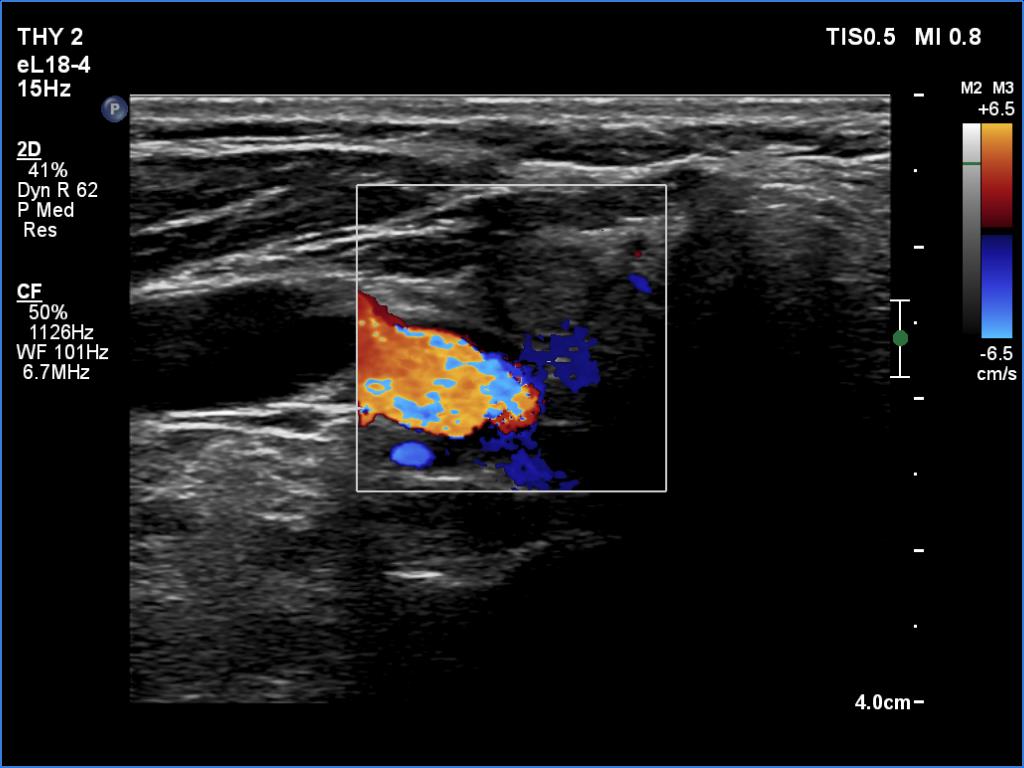

The operated thyroid - case 1700 (ultrasonographic picture 3)

Right lobe, longitudinal scan

Right lobe, transverse view, color Doppler mode. The lobe is avascular.